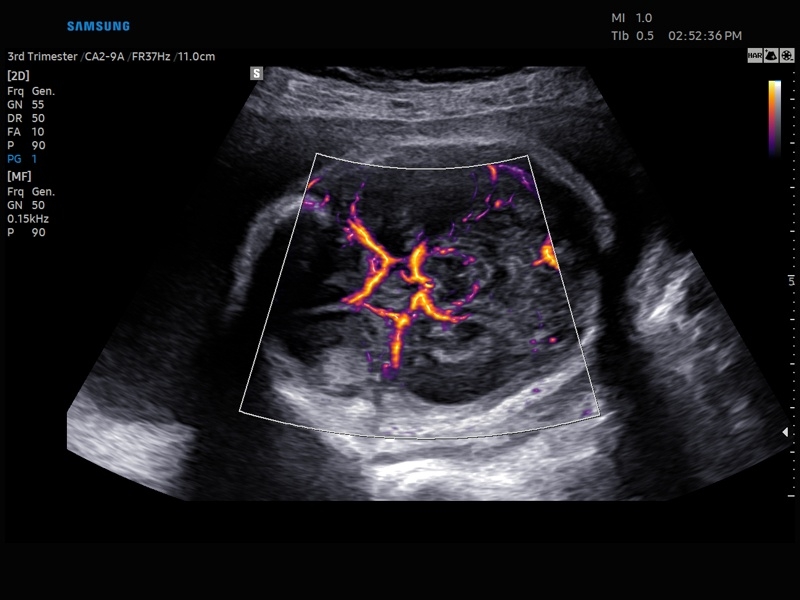

• Модуль5D HeartColor – программа автоматического построения основных срезов средца плода в режиме объемного сканирования с анализом кровотока.

• МодульSTIC- объемная динамическая визуализация сердца плода.